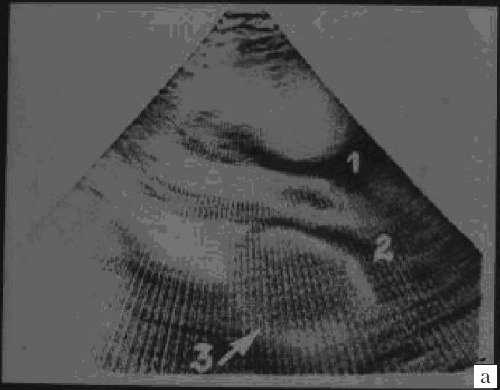

Широкое внедрение в практику ультразвуковой диагностики позволило перейти от аутопсийной статистики к прижизненному выявлению. Эхокардиография - первый метод выявления рабдомиомы сердца и контроля состояния пациента в динамике. Учитывая очень большое число семейных случаев, необходимо обследование всех ближайших родственников, особенно при наличии у них пятен цвета кофе с молоком, депигментированных по типу шагреневой кожи, параунгвальных и параореолярных фибром, ранних миом матки, инфантильных спазмов, судорожных припадков и других признаков факоматозов. При семейных обследованиях рабдомиомы сердца могут выявляться у совершенно бессимптомных носителей (рис. 1, 2).

Рис. 2. Эхокардиограмма матери этого же ребенка. В межжелудочковой перегородке несколько эхоплотных образований (стрелки).